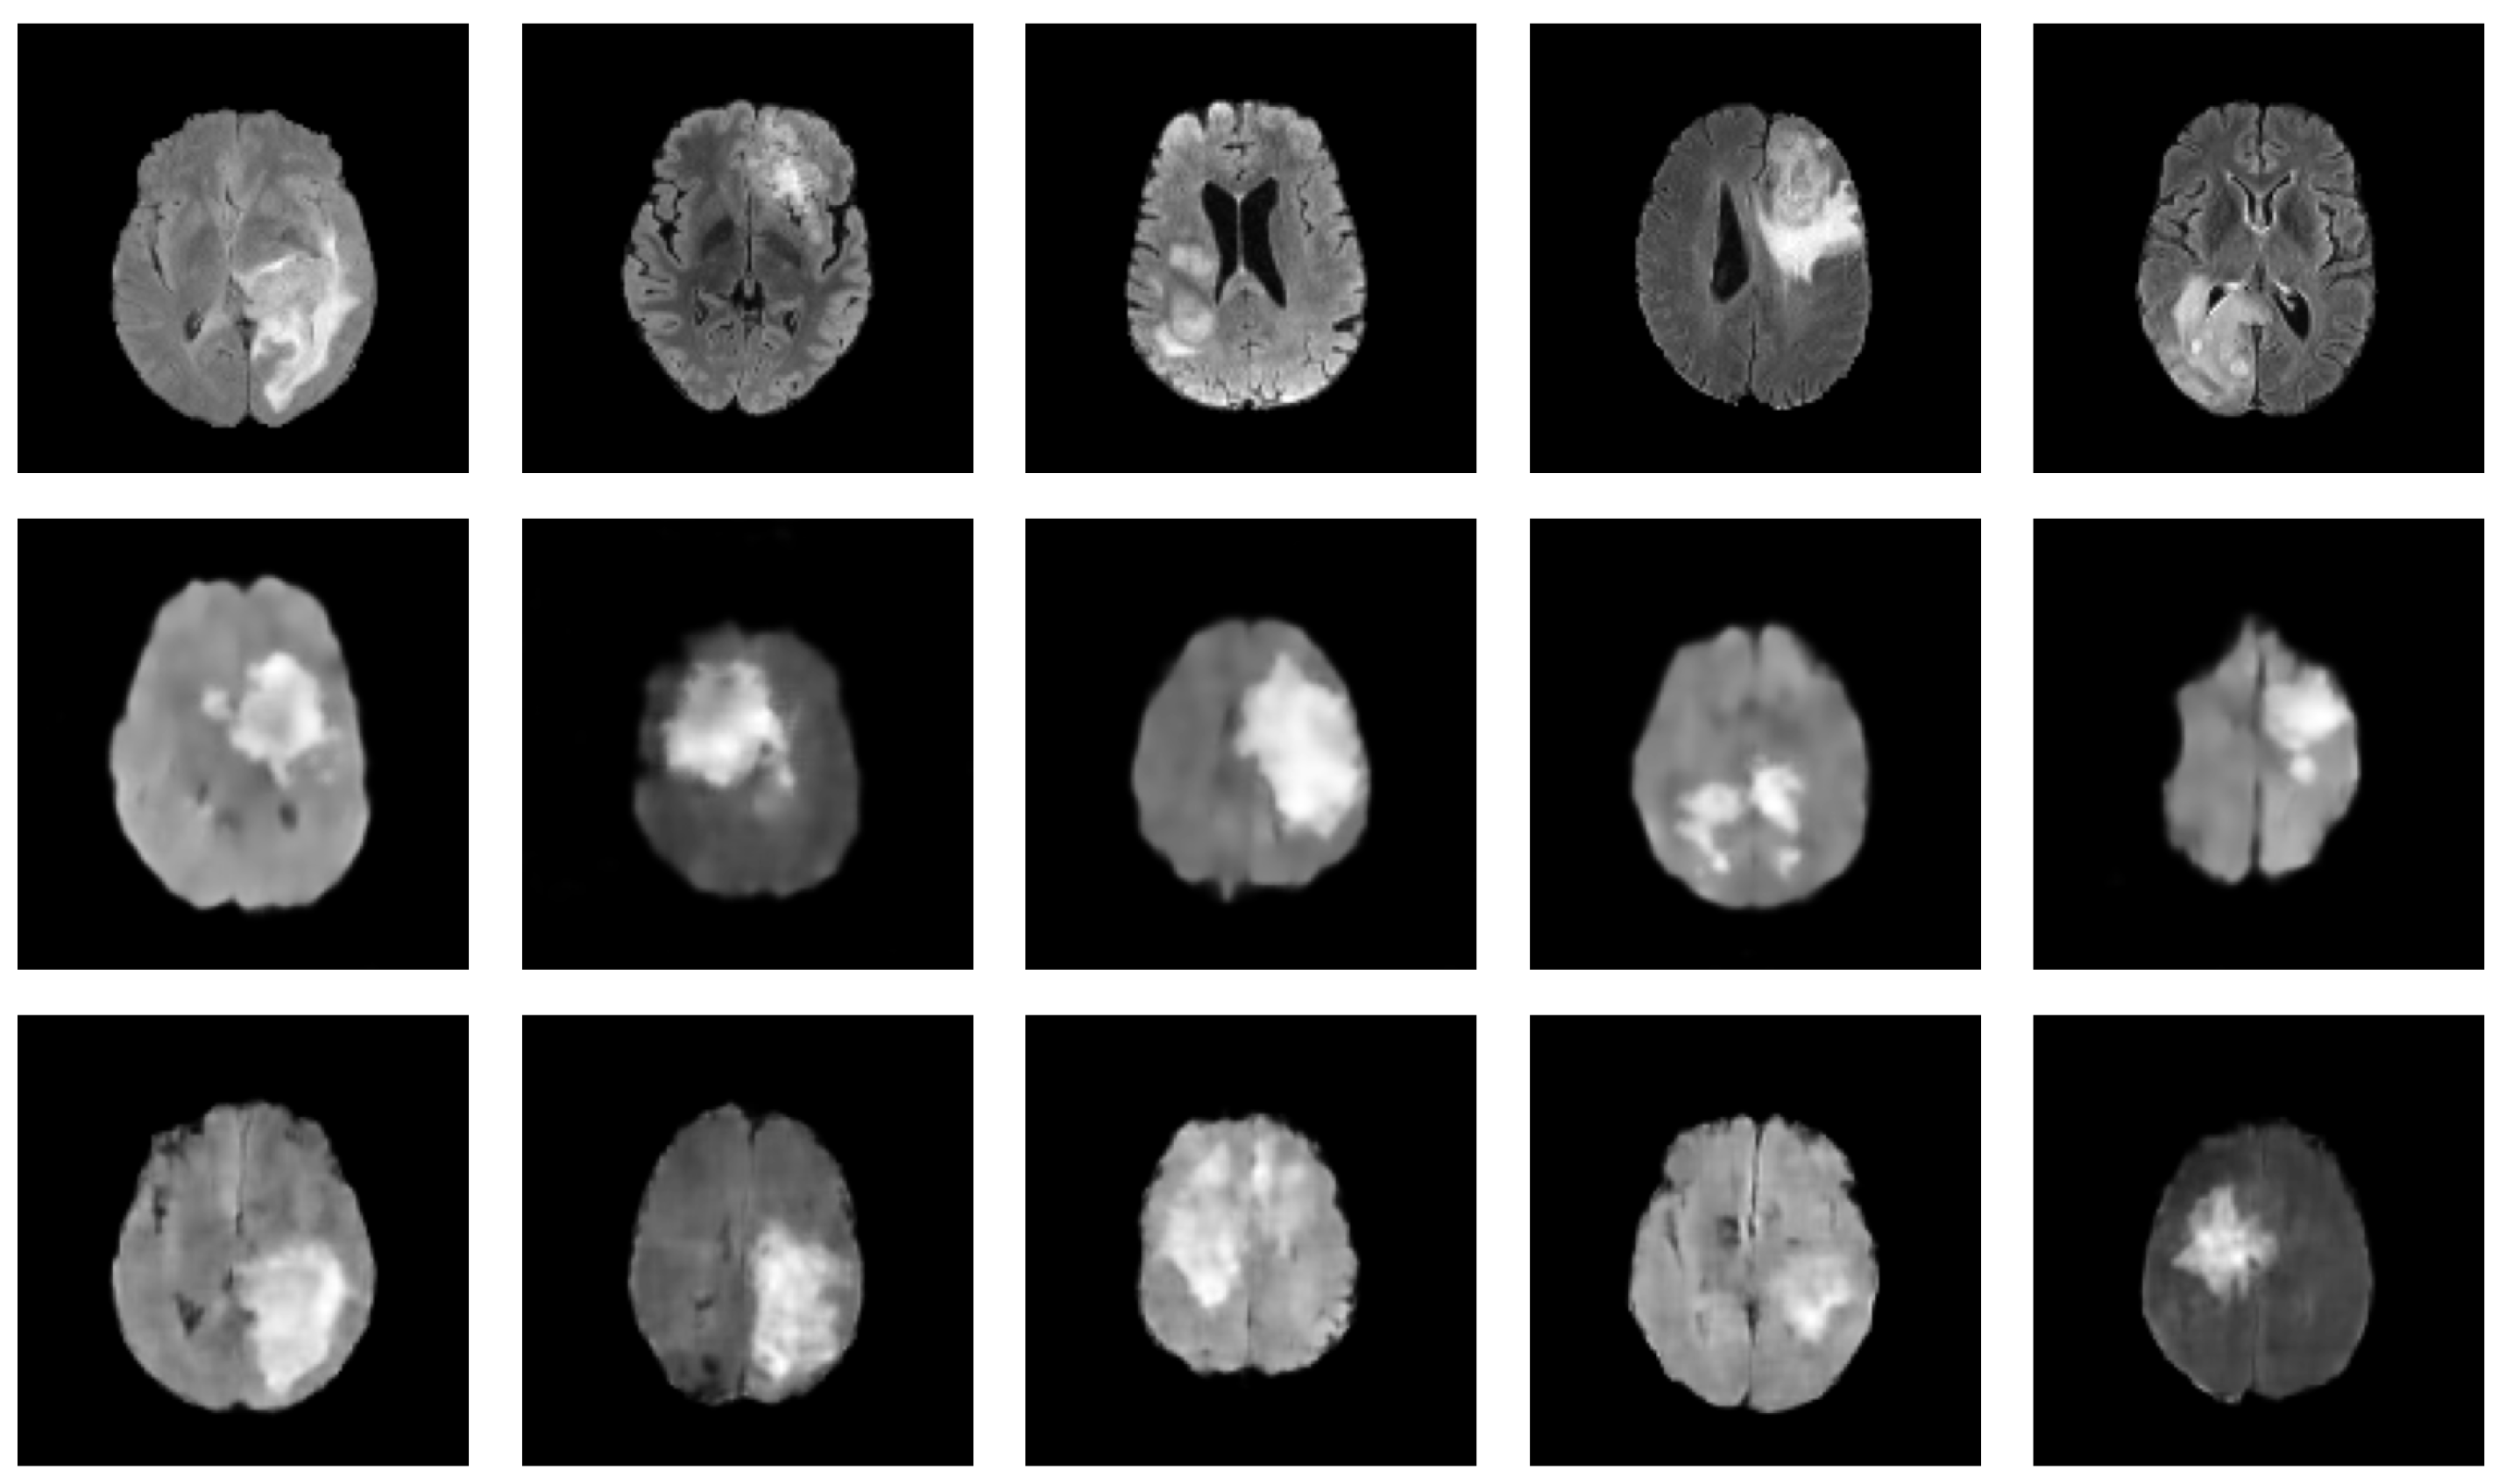

Figure 4.

Synthesized MRIs using a diffusion-based probabilistic model (DDPM) [20] trained on the BraTS2020 dataset. The first row shows a sample of original images, while the second row shows a sample of synthesized images generated using the DDPM.